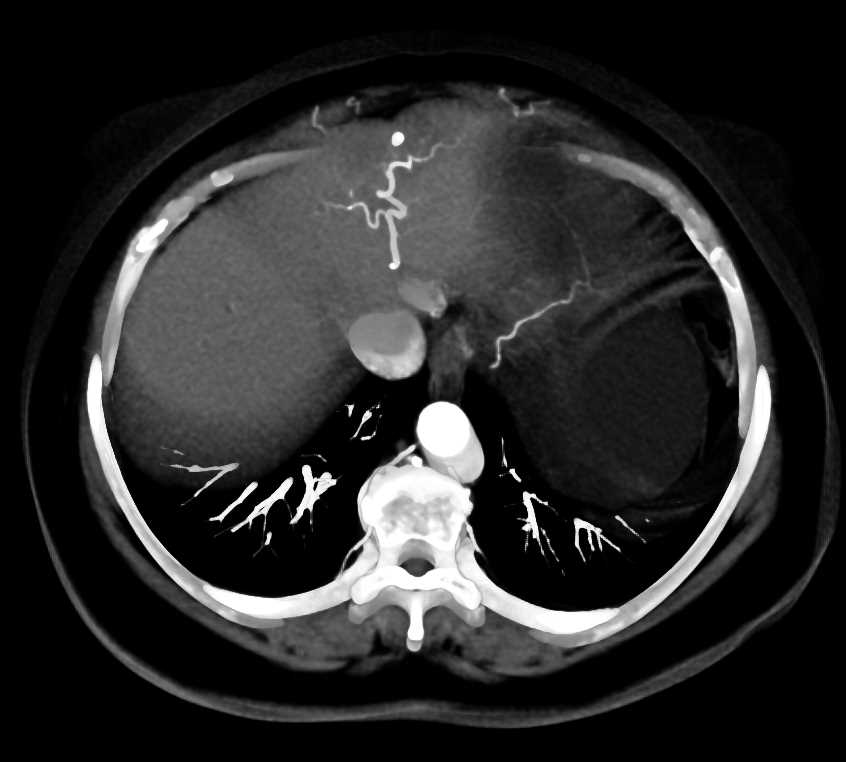

Fatty Liver Ct

CT scan slices showing extensive metastatic liver cancer Stock Photo …